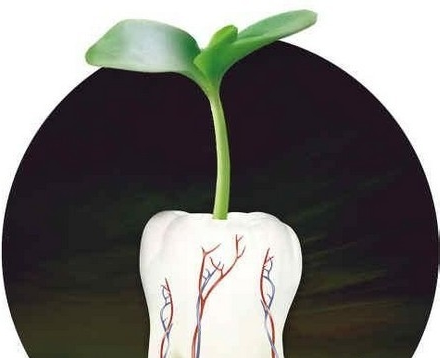

ЁЁЁЁвЛАуЧщПіЯТЃЌжжжВЪжЪѕЪєгквЛРраЁЪжЪѕЃЌМђЕЅЕФжжжВбРЪжЪѕРрЫЦАЮбРЃЌЕЋКЭАЮбРЯрБШЃЌжжжВбРЕФИаОѕвЊКУКмЖрЃЌвђЮЊАЮбРЪЧДгЙЧЭЗРяШЁГібРГнЃЌаЮГЩПЊЗХЕФДДПкЃЌМДЪЙАЮбРЕФЙ§ГЬжаВЛЬлЃЌАЮЭъбРКѓвВЛсИаОѕЩйаэВЛЪЪ;ЖјжжжВбРЪЧНЋжжжВЬхжВШыбРВлЙЧРяЃЌаЮГЩЕФЪЧЙиБеЕФДДПкЃЌжжжВЕФЙ§ГЬжаВЛЛсЬлЭДЃЌжжжВЭъГЩКѓЃЌЗДгІЗЧГЃЧсЮЂЃЌЭЌЪБдкжжжВЪжЪѕЧАжжжВбРНЬЪкЛсЮЊЛМепЪЙгУТщзэМСНјааОжВПТщзэЃЌТщзэКѓУЛгаШЮКЮЬлЭДИаЁЃ

ЁЁЁЁжжжВбРЪжЪѕДДЩЫМЋаЁЃЌЪжЪѕКѓМДПЩНјЪГЃЌМИКѕУЛгаЬлЭДЁЃЫфШЛЪѕКѓСНШ§ЬьФкгаЕФЛМепЛсГіЯжЧсЮЂЬлЭДжзеЭИаЃЌЕЋЪЧВЛгУЙ§гкЕЃаФЃЌетаЉЧщПіЖМжЛЪЧднЪБадЕФЃЌЙ§МИЬьздШЛОЭЛсЯћГ§ЁЃжжжВЪжЪѕКѓЃЌОЙ§3-4ИідТЕФЛжИДЃЌШЫЙЄбРИљгыбРВлЙЧНєУмНсКЯОЭПЩвддкШЫЙЄбРИљЩЯДїЩЯбРЙкСЫЁЃжжжВаоИДКѓЃЌживЊЕФЪЧзёеевНжіНјааПЦбЇНЁПЕЕФПкЧЛЛЄРэЃЌБЃГжЧсЫЩгфдУЕФаФЬЌЃЌЬлЭДЛсКмДѓГЬЖШЩЯЛКНтЩѕжСЯћЪЇЁЃЁЗЁЗЁЗЭЦМідФЖСЃКдкРШЗЛЃЌзіжжжВбРФмгУвЛБВзгТ№ЃП

ЁЁЁЁдкжжжВбРЪжЪѕЙ§ГЬжаЃЌЫфШЛЪЙгУТщзэМСОжВПТщзэЪЧжжжВбРЪжЪѕМѕЧсЬлЭДВЛПЩЛђШБЕФЪжЖЮЃЌЕЋбЁдёвЛУћСйДВОбщЗсИЛЁЂММЪѕзЈвЕцЕЪьЕФжжжВбРвНЩњЪЕЪЉжжжВИќЪЧгШЮЊживЊЃЌзЈвЕИКд№ШЮЕФжжжВбРвНЩњЛсШУЛМепЯћГ§НєеХЕФЧщаїЃЌЭЌЪБОЋеПЕФММЪѕЛЙФмМѕЧсЬлЭДЃЌЫѕЖЬЪжЪѕЪБМфЃЌЪЕЯжАВШЋеяСЦЁЃ